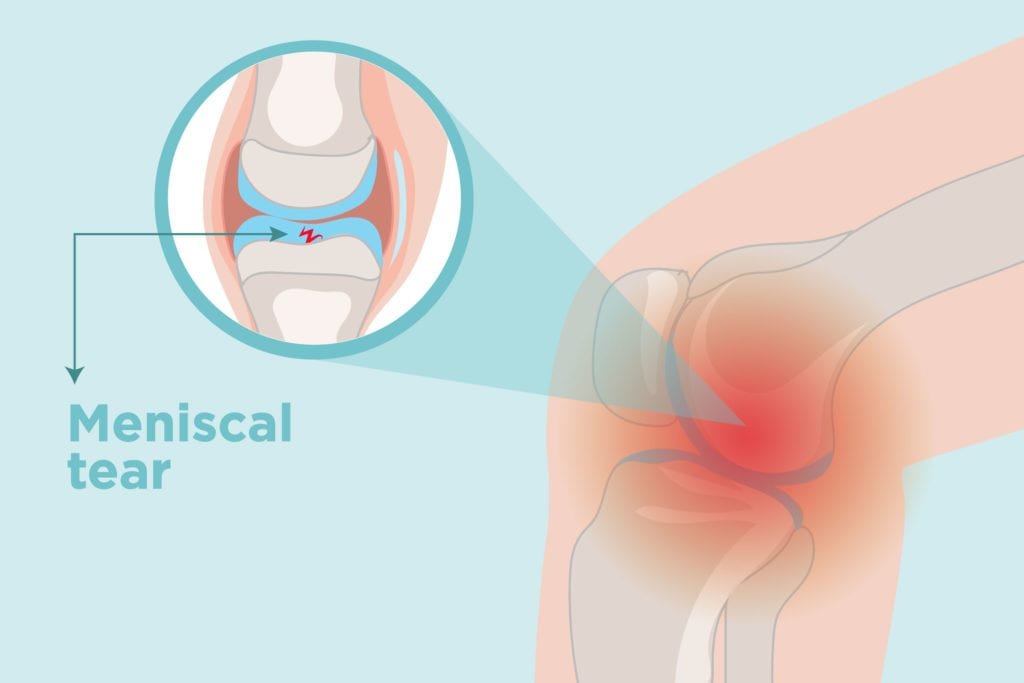

What is a Torn Meniscus?

A torn meniscus is one of the most frequent knee injuries. Any activity which causes you to forcibly twist or rotate your knee, particularly when putting your full weight on it, could result in a torn meniscus.

Each of your knees has two C-shaped pieces of cartilage which act like a cushion between your shinbone and your femur otherwise known as menisci. A torn meniscus causes pain, inflammation and solidness. You also may feel a block to knee motion and have trouble stretching your knee fully.